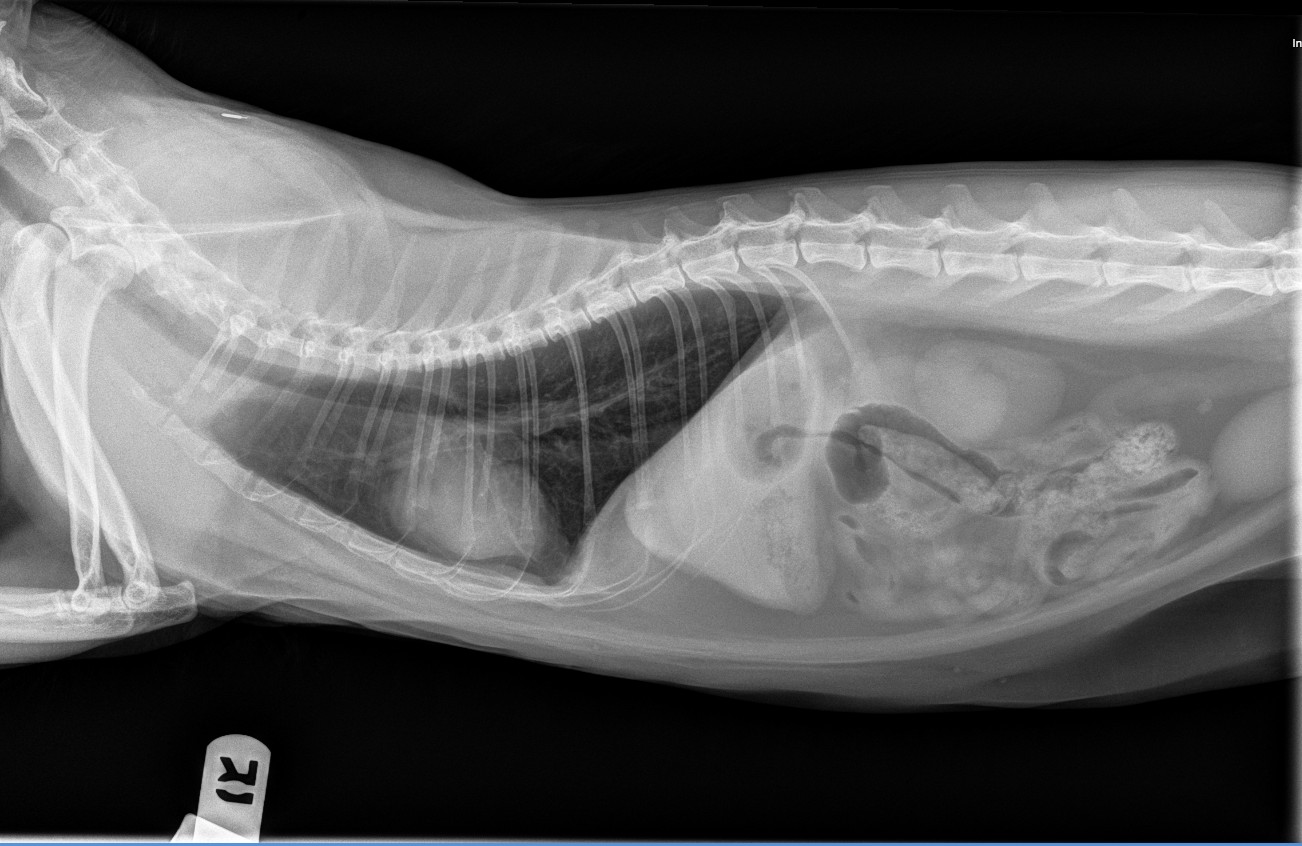

- Radiographs

- CT

In some urgent situations, pets may require surgical treatment or hospitalization. Conditions such as intestinal foreign body obstructions, bladder stones, pyometra (uterine infection), mass removal, or other acute medical concerns may need prompt surgical intervention.

Because Arbor View Animal Hospital is a full-service veterinary hospital, diagnostic testing, advanced imaging, anesthesia, and surgical care can often be coordinated in one location. Our goal is to provide efficient, compassionate care and minimize delays when timely treatment is important.